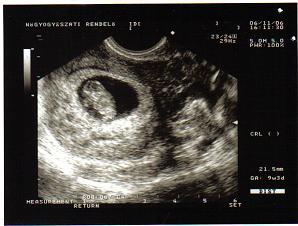

Most vagyok a 9. hétben. 21 mm-es.

Eddig azért nem tudtam hogy terhes vagyok, mert a szoptatás miatt a mensim nagyon összevissza jött meg, így nem csodálkoztam hogy kimaradt. De aztán állandóan hányingerem volt (van), meg hánytam is. Meg nagyon kívánom a savanyúságot. Szóval csináltam 1 tesztet, ami pozitív lett. Ma elmentem EZS-hoz, és minden rendben.